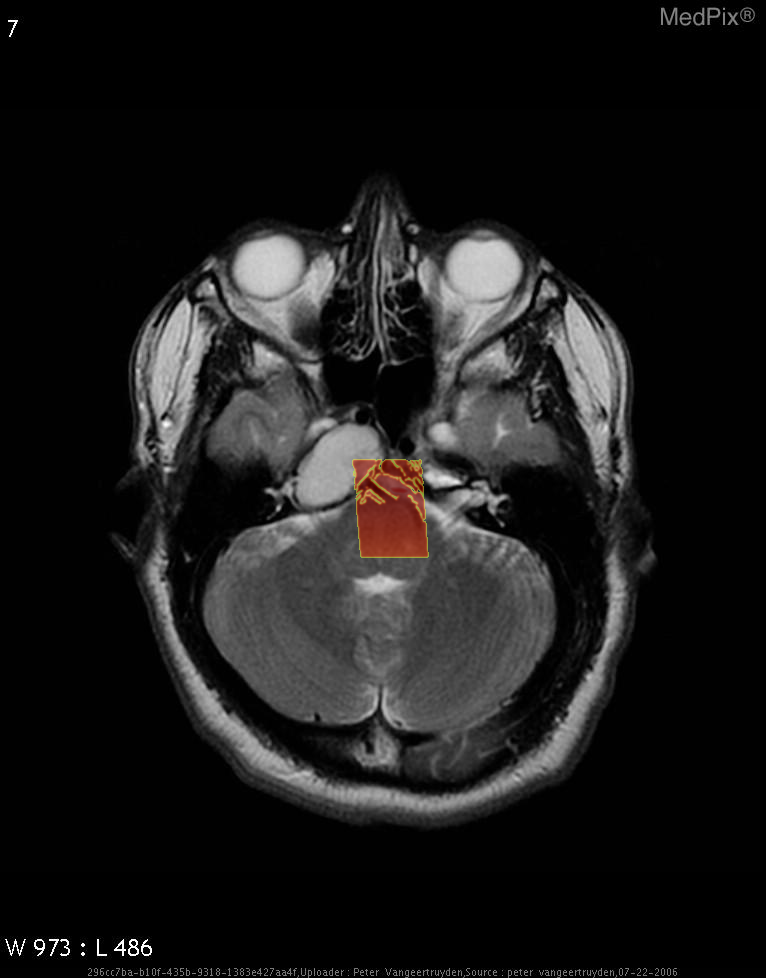

Base slice Focus overlay CLIP overlay

Low confidence

High confidence

- Axial MRI brain shows a large, well-defined, expansile lesion centered in the petrous apex region on the image-left (patient-right).

- Lesion demonstrates homogeneously high signal intensity on T2-weighted sequence, suggesting fluid or blood product content.

- The mass appears to cause remodeling and expansion of the petrous temporal bone on the image-left (patient-right).

2) Most likely diagnosis and why:

Cholesterol granuloma of the petrous apex (image-left = patient-right). This diagnosis is favored due to the well-circumscribed expansile lesion in the petrous apex with homogeneous T2 hyperintensity and smooth bony expansion, typical for a cholesterol granuloma containing blood degradation products. No solid component or irregular enhancement pattern suggests a cystic, benign process rather than neoplastic. Context consistency: Consistent — matches the provided context of petrous apex cholesterol granuloma in a 64-year-old female. Confidence: 90%